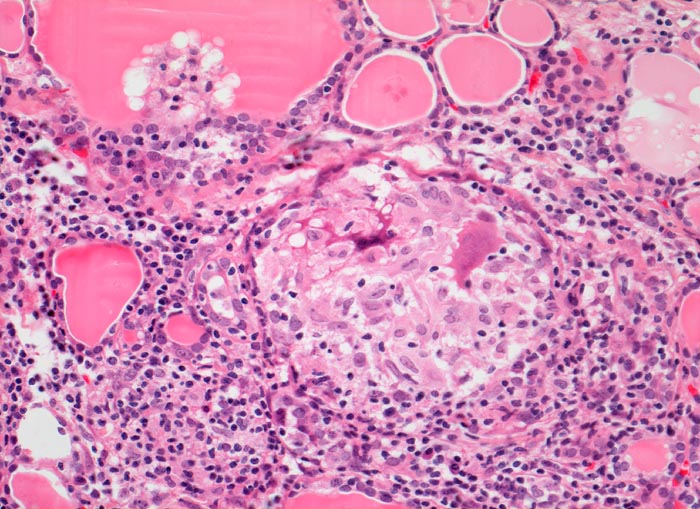

AP/ Subakute Thyeroiditis de Quervain

Subakute Thyeroiditis de Quervain

Schilddrüse

Pathologischer Befund